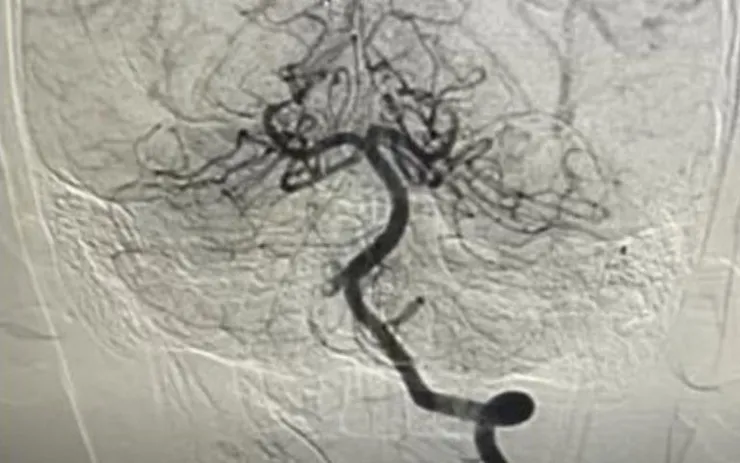

Ngay sau hội chẩn liên khoa, các bác sĩ chỉ định chụp mạch máu não số hóa xóa nền (DSA) và can thiệp nội mạch cấp cứu. Ekip do BSCKII Trần Công Bảo Phụng thực hiện đã tiến hành tiêu sợi huyết tại chỗ kết hợp hút huyết khối, tái thông hoàn toàn mạch máu não cho bệnh nhi.

Sau can thiệp, tình trạng lâm sàng cải thiện rõ rệt: trẻ tỉnh táo, sinh hiệu ổn định, chức năng vận động phục hồi nhanh. Sau một tuần điều trị, bệnh nhi có thể vận động gần như bình thường, chưa ghi nhận di chứng thần kinh.